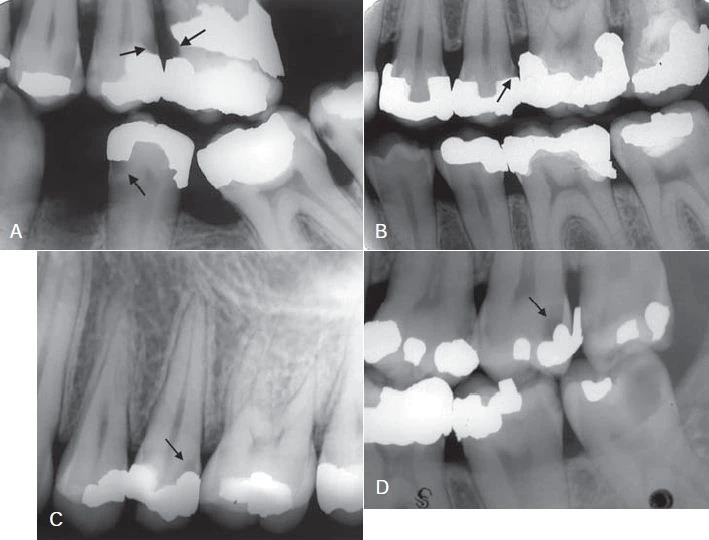

SÂU RĂNG LIÊN QUAN ĐẾN PHỤC HỒI NHA KHOA

Một tổn thương sâu răng phát triển tại bờ của miếng trám có thể được gọi là sâu răng thứ phát hoặc tái phát. Cần lưu ý rằng mặc dù tổn thương này phát triển trên bề mặt đã được phục hồi thì hầu như luôn có một quá trình mất khoáng mới, hoặc là do lỗi sai trong việc tạo hình hay mở xoang trám không tốt dẫn đến tích tụ mảng bám. Những tổn thương như vậy (sâu răng thứ phát) cần được điều trị như một sâu răng mới. Điều quan trọng là không nhầm lẫn giữa sâu răng thứ phát và sâu răng còn sót lại – sâu răng vẫn còn do tổn thương ban đầu không được loại bỏ hoàn toàn. Trong trường hợp trên X quang cho thấy tổn thương rất gần với tuỷ răng, phần ngà sâu có thể để lại có chủ định trong suốt quá trình điều trị. Thuốc có tác dụng kích thích sự phát triển của ngà răng được đặt trong xoang trám (che tuỷ gián tiếp). Sau một vài tháng, phần ngà sâu còn lại sẽ được loại bỏ và thay bằng chất trám vĩnh viễn.

Một tổn thương cạnh miếng trám có thể bị che lấp bởi hình ảnh X quang của miếng trám. Vì vậy cần chụp hai phim X quang với những góc độ dọc hoặc ngang của tia trung tâm khác nhau nhằm thấy được nhiều góc độ cản quang của miếng trám. Ngoài ra, để phát hiện ra tổn thương sâu răng còn tuỳ thuộc vào việc thăm khám lâm sàng cẩn thận. Tổn thương tái phát tại bờ nướu phía gần và xa thường phát hiện được trên X quang.

Vật liệu trám có hình ảnh cản quang khác nhau tuỳ thuộc vào bề dày, mật độ, số lượng nguyên tử và năng lượng nguồn tia X khi chụp. Một số vật liệu có thể bị nhầm lẫn với sâu răng. Những chất lót canxi hydroxide không chứa barium, chì, hoặc kẽm (được thêm vào để tăng độ cản quang) có hình ảnh thấu quang và có thể nhầm lẫn với sâu răng tái phát hoặc sâu răng sót lại. Mặc dù có sự hiện diện của canxi, phần lớn vật liệu có nguyên tử lượng thấp trong canxi hydroxide có độ cản quang tương tự như sâu răng. Composite, nhựa hoặc chất trám silicate cũng có thể giả dạng sâu răng. Thường có thể nhận biết và phân biệt những vật liệu thấu quang này với sâu răng bằng đường viền liên lục, rõ nét cho thấy có sự sửa soạn xoang trám hoặc đường trám lót cản quang.

Hình 17. Sâu răng cạnh miếng trám.

Hình 18. Vật liệu trám không cản quang